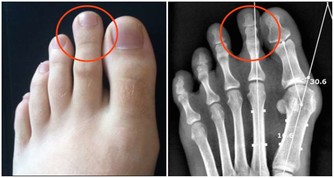

根據調查顯示:痛風患者的初發平均年齡在不到20年的時間裡下降了6.3歲,開始襲擊年輕人。據分析發現,痛風的初次發病年齡有明顯年輕化的趨勢,不足40歲的初次發病者增加了26.3%。

年輕人患痛風的原因是什麼呢?專家認為,攝入富含嘌呤類食物(含有嘌呤代謝紊亂的食物如動物內臟,魚蝦蛋白以及啤酒等,肝,腎,肉餡,肉汁,肉湯,鯖魚,風尾魚,沙丁魚,魚卵,小蝦,淡菜,鵝,斑雞,石雞等含嘌呤都很高,再者熏火腿,豬肉,牛肉,兔肉,鴨,鴿,貝殼類含嘌呤也是比較高的,如果有痛風就不建議吃這些食物。)者迅速增多是主要原因。人們的飲食結構已經發生了明顯的變化,尤其是20歲至40歲的年輕人飲食中含高能量、高嘌呤類物質者顯著增加。數據顯示:20歲至40歲年齡組的痛風病人發病前,90%以上有經常大量飲酒和嗜好吃肉、動物內臟、海鮮等富含嘌呤類成分食物的習慣。

調查發現,在40歲以下的痛風患者中,約85%的人體重超重。由於工作繁忙等原因,在40歲以下的痛風人群中,多數人起居不規律,體力活動越來越少,出門坐車者增多,騎自行車、步行者漸少。生活富裕,又缺少足夠的體育鍛煉,肥胖是必然的趨勢。研究結果證明,血尿酸水平與體重指數呈正相關。